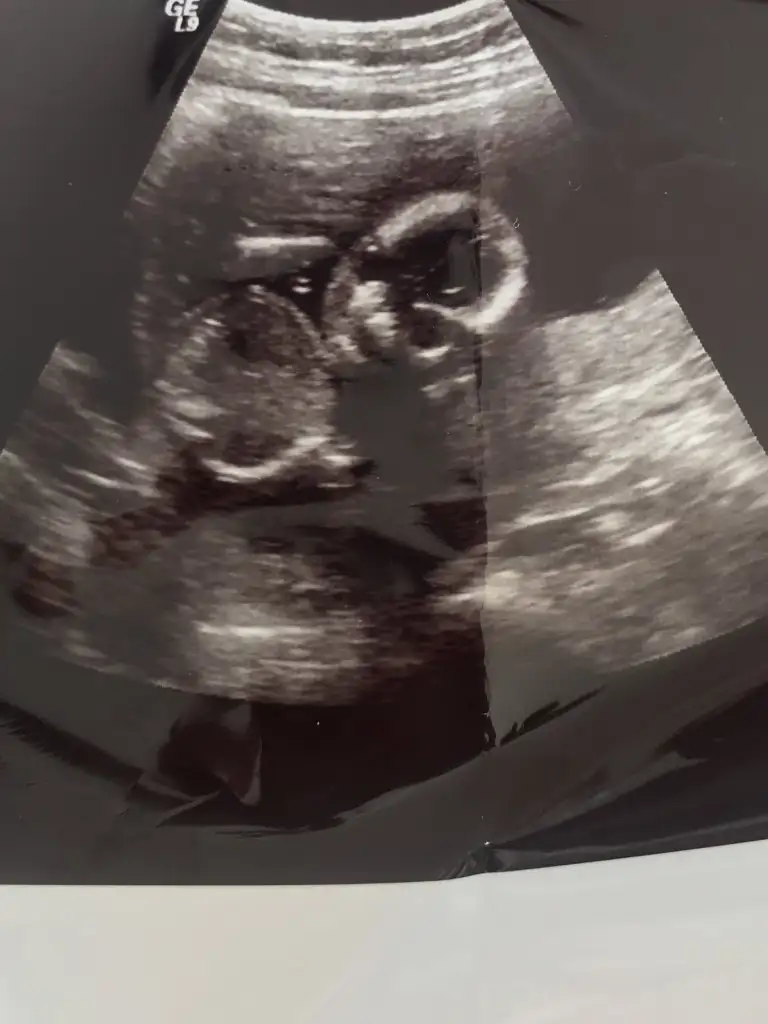

Evet erkek dik görünüyorLütfen bana da yorum yapar mısını?doktor erkek olabilir dedi 12+1 deki ve 12+4 deki ultrason resimleri

Kese yapısı değişiyormu acaba surekli fasulye seklini yuvarlak gordum dger gün şaşrdmErkek gibi ama en iyi 11 12 13 haftalar olmalı

Elimdeki son usg bu, çok net değil ama belki siz görebilirsiniz.Sağlıkla gelsin yinede göstereyim çizdim usgnizi az önceben şok demekki pozisyon la alakalı değişim oluyor Eki Görüntüle 2726610

Hem net değil hem 14 den sonra organı oluşuyorElimdeki son usg bu, çok net değil ama belki siz görebilirsiniz.

Kaç haftalikta Dr kiz dedi tabiki sağlıkla gelsin minnosElimdeki son usg bu, çok net değil ama belki siz görebilirsiniz.

Net değil tekrar USG paylaşın 12-13 hafta olursa şimdilik sanki kız yönünde nubuMerhaba Ikra meyra biz 11+3 günlüğüz tahminin varmı acaba doktorumuz bişey demedi teşekkürler şimdiden

16+3 te kız dedi, bu son attığım da son usg. Hatta 17 haftayla uyumlu bebişim.Kaç haftalikta Dr kiz dedi tabiki sağlıkla gelsin minnos

Evet USG çizdim gördüyseniz16+3 te kız dedi, bu son attığım da son usg. Hatta 17 haftayla uyumlu bebişim.